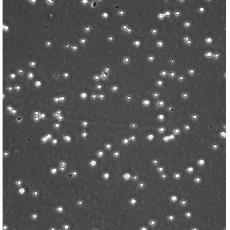

生長特性 suspension

形態特征 lymphoblast

細胞描述 CEM/C1是人T細胞白血病細胞株CCRF-CEM(見ATCC CCL-119)具有喜樹堿抗性的衍生株。1991年細胞株選擇并亞克隆了對CPT的抗性。細胞表現出對CPT類似物水溶性的托泊替康和非水溶性的9-氨基-CPT及10,11-亞甲二氧基-CPT具有交叉抗性。CEM/C1細胞對CPT的敏感性較母系CEM細胞低31倍。CEM/C1細胞表現非典型的多藥抗性和轉換拓補異構酶I催化活性。對CPT的抗性維持6個月以上。